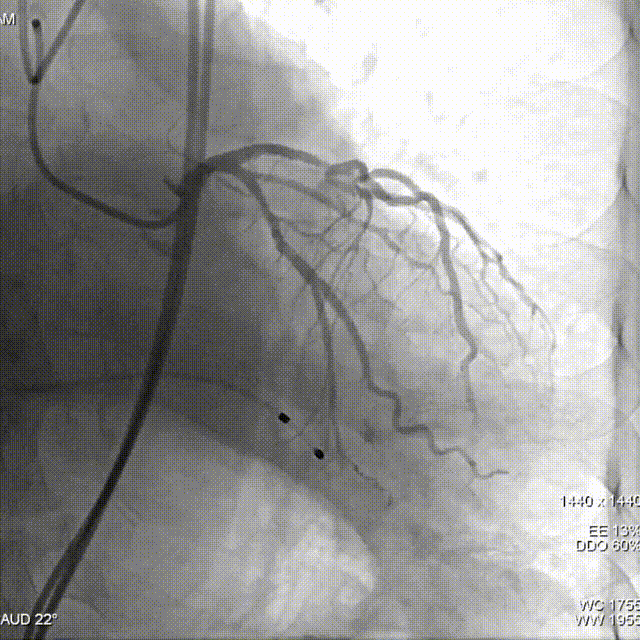

冠脉造影